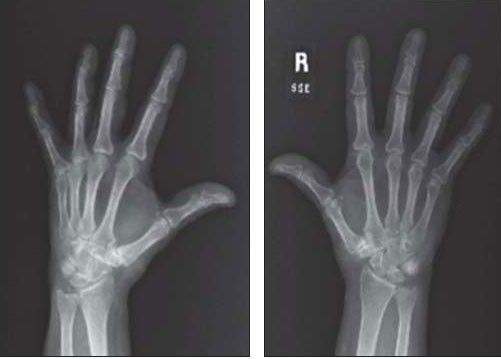

A 69-year-old woman presented with a 5-year history of bilateral knee pain with symptoms initially attributed to osteoarthritis and then to rheumatoid arthritis. She had a history of asymptomatic Paget disease of bone. Physical examination revealed tenderness, swelling, and crepitation in both knees. X-ray films of the patient’s hands showed chondrocalcinosis of the triangular fibrocartilage, and chondrocalcinosis was seen on pelvic and knee films.

Paget disease of bone was thought to play a role in the development of her disorder.